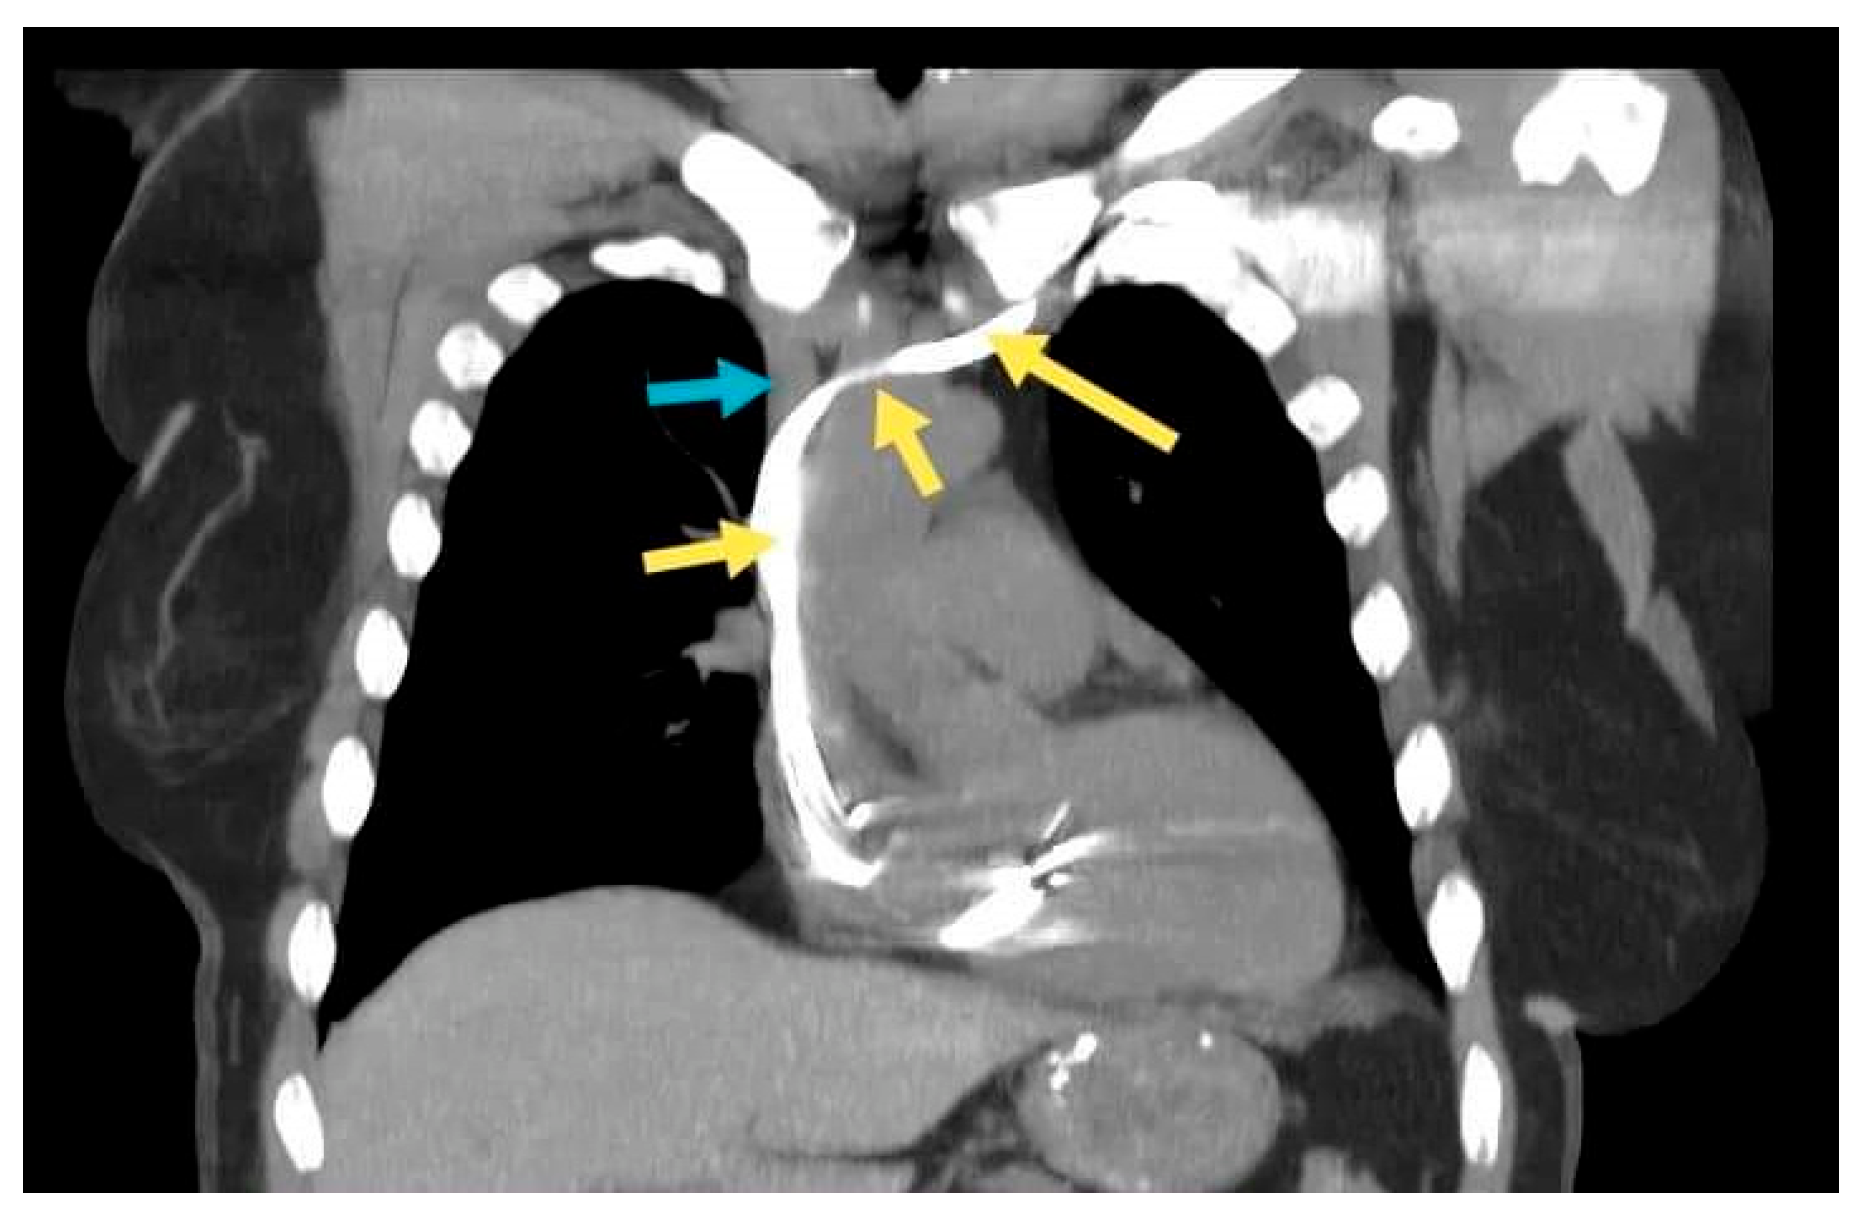

A 66-year-old female patient diagnosed with sick sinus syndrome (tachycardia–bradycardia syndrome: sinus bradycardia alternating with paroxysmal atrial fibrillation (AF)), based on 24 h ECG Holter monitoring, symptomatic through repetitive syncope, fatigue, and palpitations, was referred to our clinic for the implantation of a pacemaker. During the dual-chamber pacemaker implantation, the abnormal route of the guide wires was noticed, and we decided to perform a venography through the subclavian vein already punctured (Figure 3a). This not only confirmed the presence of persistent left superior vena cava, but also a communication with the right superior vena cava through a small vein called the innominate vein (type IIIa). Faced with this situation, we decided to approach this small caliber vein to facilitate the implantation of the leads without passing through the coronary sinus. First of all, we managed to insert the guide wires into this vein using rotational movements, and for the leads we used a straight stylet. After reaching the atrium, we passed the tricuspid valve with a specific stylet, and the lead was placed at the right ventricular septum. Finally, the second lead was placed in the right atrial appendage (RAA) (Figure 3b). A thoracic angio-CT was performed, to better characterize the venous anomaly (Figure 4).

Figure 4.

Coronal section. The yellow arrows: the lead in the subclavian vein, persistent left superior vena cava, the innominate vein, and the right superior vena cava. The blue arrow: the right brachiocephalic vein.